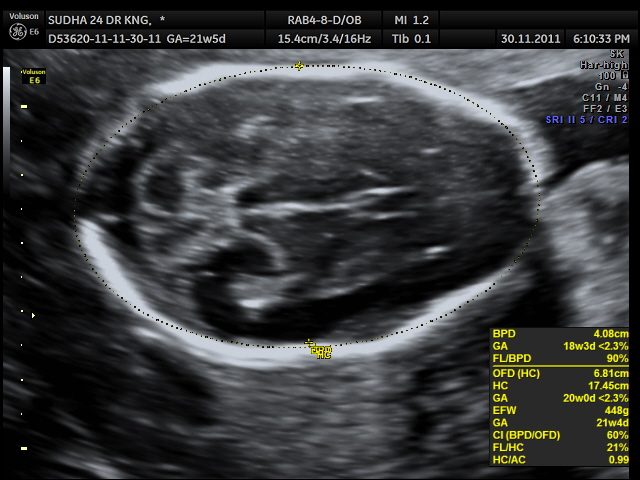

microcephaly (BPD &HC are less than <2.3 %tile )

occipital encephalocele